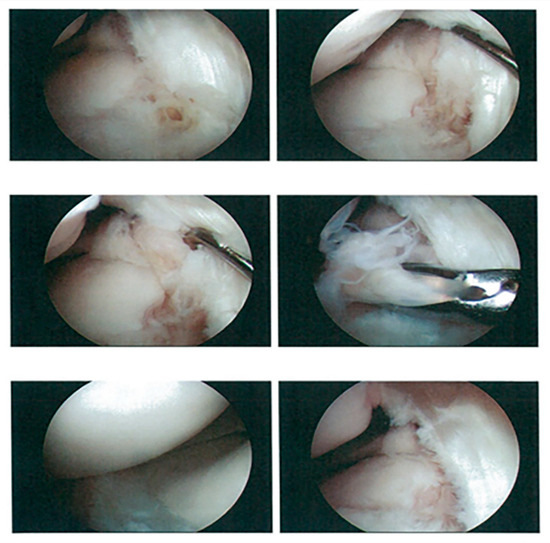

2.2. Surgical Procedure